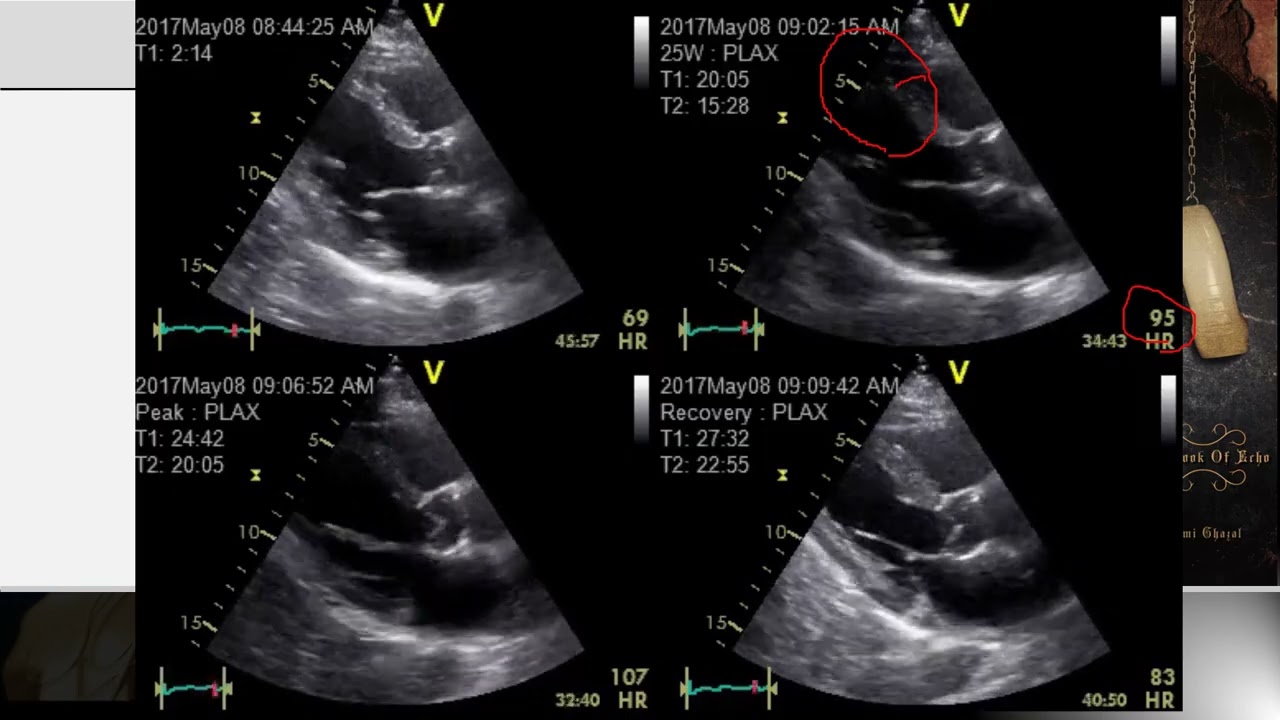

Lecture 16 - LV Pathologies Part I

Overview of LV pathologies, including ischemic complications ( aneurysm, pseudoaneurysm, myocardial dissection, ischemic cardiomyopathy), dilated cardiomyopathy, and non-compaction cardiomyopathy.